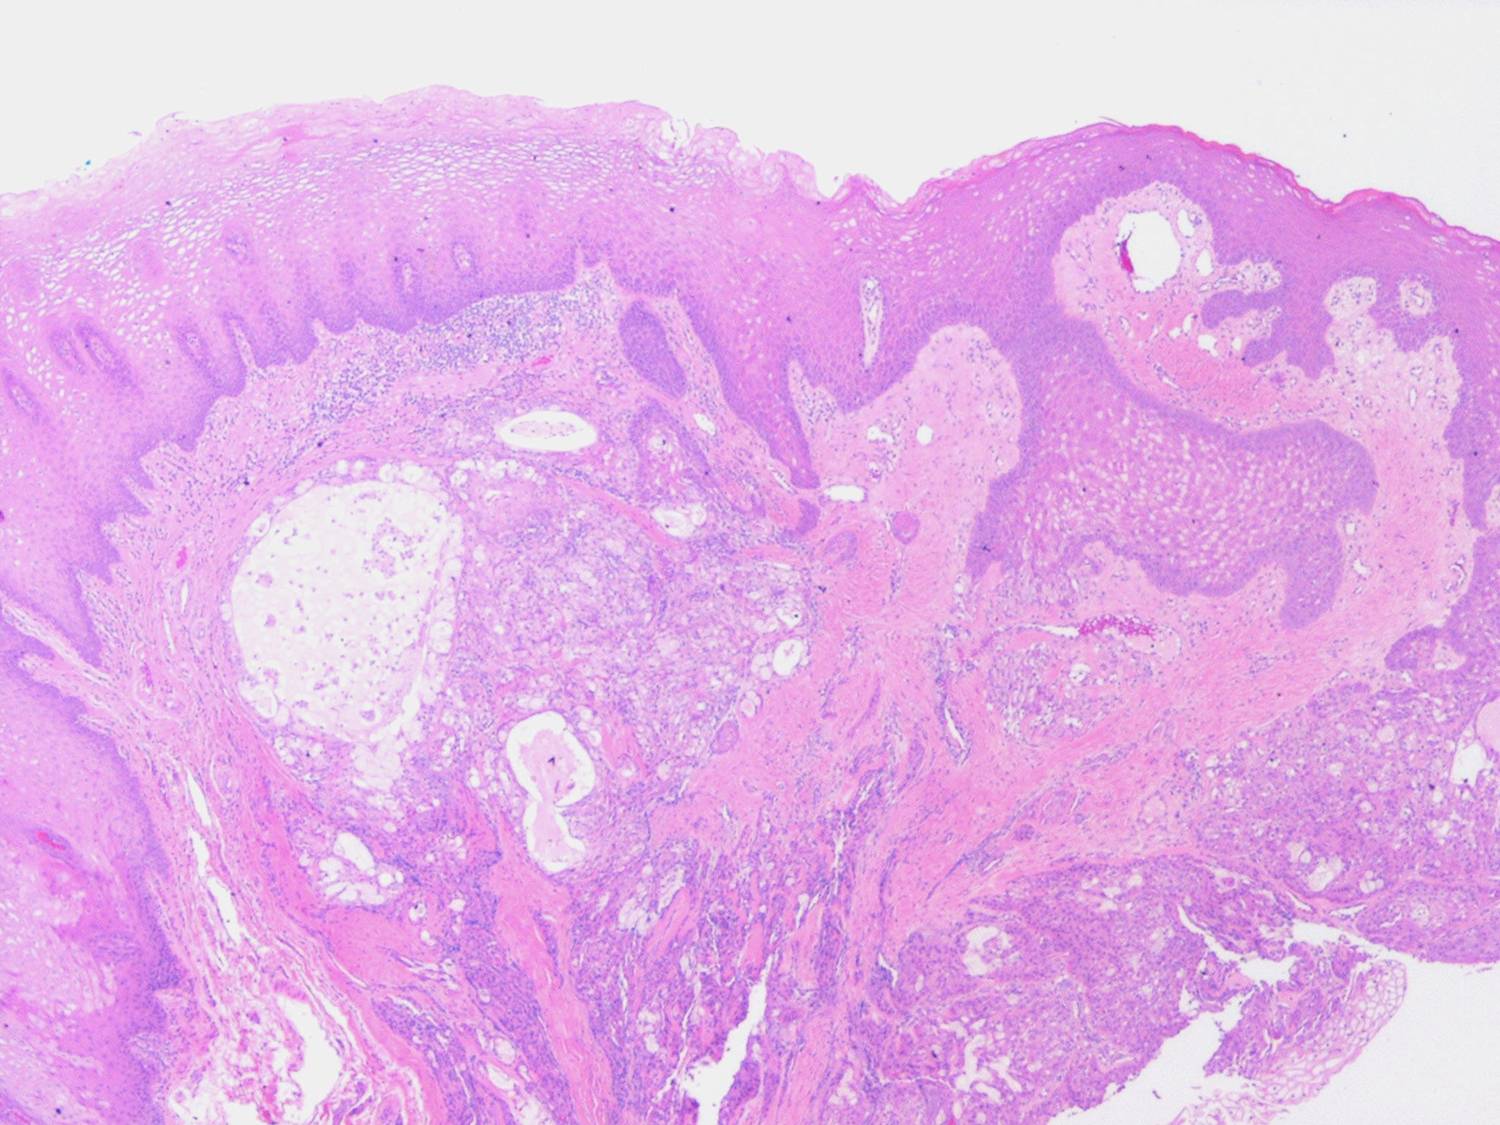

Mucoepidermoid carcinoma =الكارسينوما المخاطية البشروانية